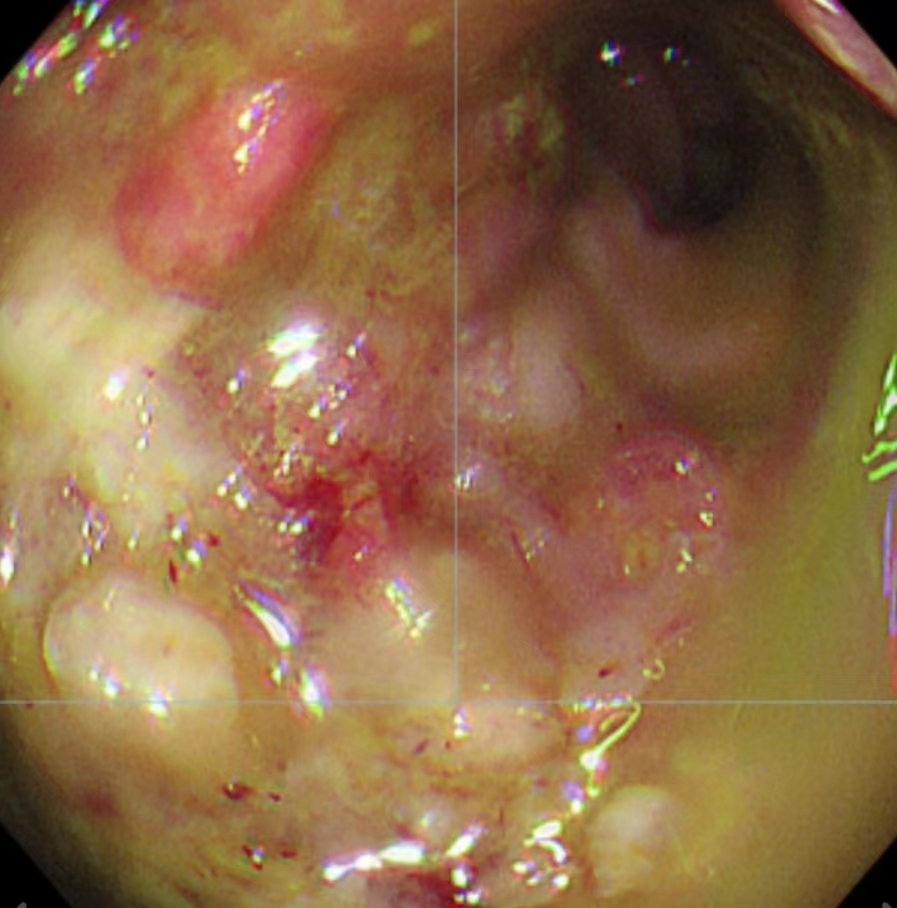

一位80岁高龄患者在一年余前于家中无明显诱因下突发腹部胀痛不适,疼痛呈阵发性,不剧,当时未予以重视。之后反复腹胀腹痛一年多,后期每日解大便数次较前增多,且每次解大便不通畅、不尽感明显。由于老年人对该疾病不敏感,一直误以为肠胃炎,没有及时就医。近期上述症状较前明显加重,遂来温州市中心医院就诊住院,查肠镜发现直肠内一较大的不规则隆起肿块,易出血,已造成肠腔狭窄梗阻,肠镜活检病理提示直肠腺癌。且进一步的腹部CT、MRI检查发现直肠肿瘤已明显侵犯右侧输尿管,导致右肾积水、右输尿管明显扩张。

肠镜检查